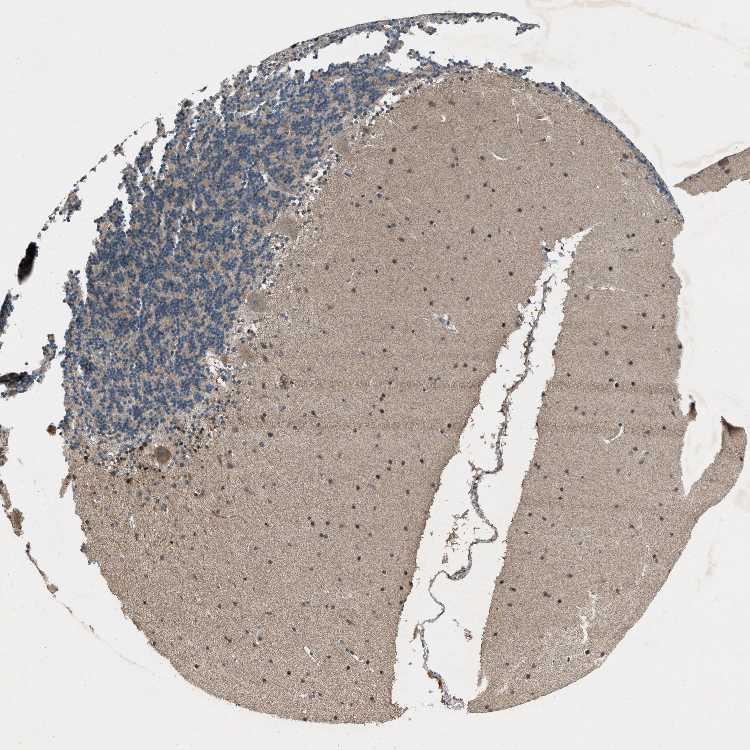

CEREBELLUM - Antibody stainingi

Antibody staining in the annotated cell types in the current human tissue is reported as not detected, low, medium, or high, based on conventional immunohistochemistry profiling in selected tissues. This score is based on the combination of the staining intensity and fraction of stained cells.

Each image is clickable and will lead to virtual microscopy that enables deeper exploration of all samples and also displays staining intensity scores, fraction scores and subcellular localization as well as patient and tissue information for each sample.

Antibody HPA017362

Purkinje cells High

Cells in granular layer Low

Cells in molecular layer Medium